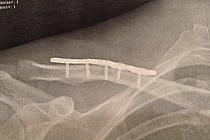

Kontuzja - jak przetrwać ten trudny czas?

Kontuzja w świecie sportu wywołuje wiele negatywnych emocji. Złość, bezradność, rozgoryczenie, rozpacz to tylko niektóre z towarzyszących sportowcom odczuć. Nie pierwszy raz doświadczam podobnego stanu. Złamany obojczyk pokrzyżował moje plany w końcówce sezonu i pozbawił mnie długo oczekiwanego wyjazdu na Lazurowe Wybrzeże i startu w Roc d’Azur! Co więcej, uziemił mnie na dobre kilka tygodni, których operacyjnie zespolona kość potrzebuje do pełnego zrostu. Najpierw akceptacja... Narzekanie i rozczulanie się nad sobą jeszcze nikogo nie uzdrowiło. Czasu cofnąć się...